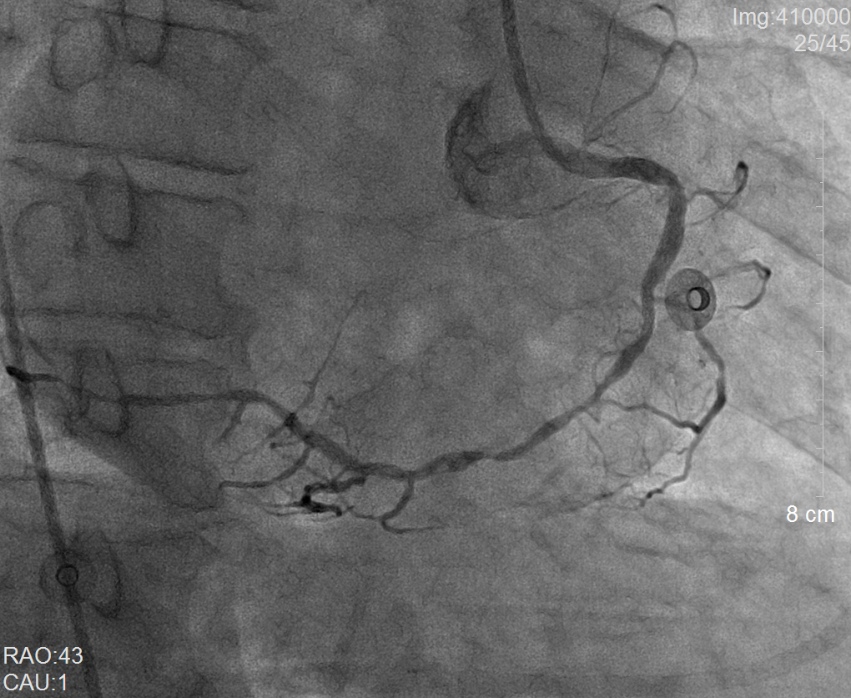

術前冠脈造影提示右冠狀動脈彌漫性病變                 術后冠脈造影提示右冠狀動脈血流通暢

當地縣醫院立即通過胸痛中心急救系統向我院心內科發出求助。當日二線值班的副主任醫師謝泓及住院總醫師李愛娜了解情況后當即決定將患者轉入我院,備行急診經皮冠狀動脈介入治療(PCI)。而值急診介入班的彭峰副主任醫師和蔡瀚醫師得知消息后也立即趕往待命。風馳電掣的120急救車一到達醫院后,接診醫生立即將林先生送往介入手術室。不料,術中冠脈造影提示林先生為極其罕見的“右位心合并急性心肌梗死”,這無疑大大增加了手術的操作難度。憑借心內科介入組醫護人員平日的訓練有素和嫻熟配合,很快就為林先生開通了“犯罪血管”——右冠狀動脈,從進入醫院大門至球囊打通血管的時間(D-to-B)僅僅60分鐘(國際標準為<90分鐘)。

在開通“犯罪血管”后,林先生出現應激性潰瘍,嘔吐大量鮮血,被緊急送至心內科重癥監護病房(CCU)搶救。消化內科鄭瑋瑋醫師為林先生在床邊行急診消化內鏡并在內鏡下止血,這才停止了嘔血。同時,林先生還合并嚴重的肺部感染和心衰,經過呼吸內科陳公平主任醫師多次精準調整抗生素和心內科重癥醫學團隊的精細救治,術后第11天,患者肺部感染和心衰就得到了良好的控制,并于1月29日進行了第二次PCI治療。距急診手術后第13天,林先生病情穩定,順利出院。